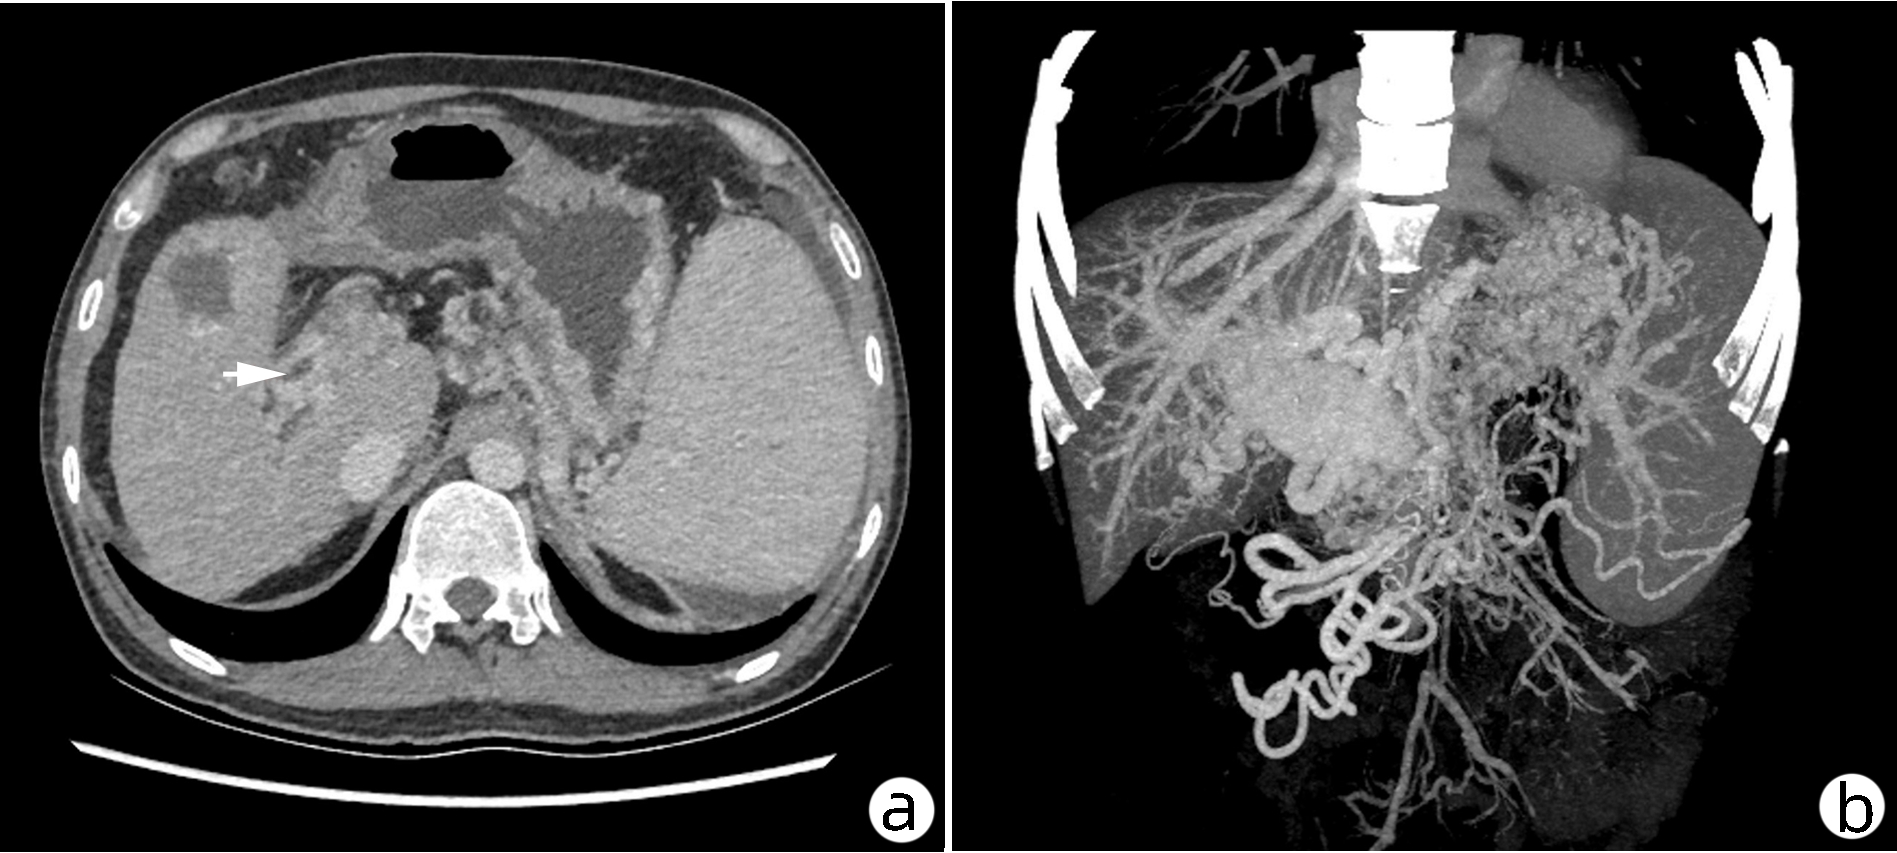

A case of idiopathic portal hypertension with psoriasis

Hui ZHOU, Bin NIU, Xiaoying ZHANG, Wei CHEN, Yuqiang MI, Ping LI

2023, 39(2): 383-386. DOI: 10.3969/j.issn.1001-5256.2023.02.020

Abstract(1167) HTML (526) PDF (3689KB)(114)

Abstract: